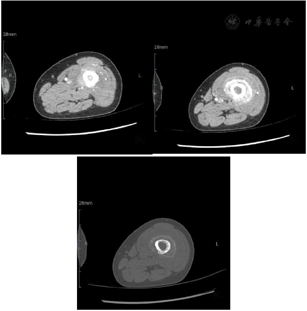

入院前查下肢彩超示:左股骨中下段骨皮质浅方实性占位。入院后查左股骨全长正侧位片示:左股骨中段骨质密度稍显减低,骨皮质毛糙、变薄,周围软组织肿胀,关节对应关系良好。查肌骨超声所见图1:左侧股骨中下段骨长轴纵切面骨皮质局部骨膜增厚,不规则隆起,可探及范围约157 mm×17 mm混合回声区,后方回声减低,交界处的骨膜回声增强、增厚、抬高呈"Codman"三角征;围绕骨干横切面见"轮辐样"放射状分布的针状强回声,回声与骨皮质表面垂直;彩超多普勒血流显像(color Doppler flow imaging,CDFI):内可探及星点状血流信号;后方骨皮质尚连续,中下段边缘毛糙。进一步查左股骨中下段增强CT所见图2:左股骨中下段髓腔内见纵形软组织密度影,邻近骨皮质稍增厚且骨质密度减低,呈筛孔样骨质破坏,周围可见放射状骨膜反应及软组织肿块,骨干未见明显膨胀,增强扫描后髓腔内见穿行血管影,周围软组织肿块中度强化。查左股骨中下段核磁见图3:左股骨干中下段髓腔内条带状长T1、压脂长T2信号影,骨皮质厚薄不均,信号欠连续,压脂信号增高,骨干周围包绕软组织块,呈略短T1、压脂长T2信号影,压脂T2其内见多发细线样低信号影垂直于骨皮质分布,病变与周围软组织区界限不清,软组织内片状长T1、压脂长T2信号影;扫描所示左股骨干远端小圆形、右股骨干中段髓腔内条带状长1、压脂长T2信号影,境界较清晰,邻近骨皮质未见明确异常。查胸部CT见图4:双肺纹理增重,双肺见多发大小不等结节样高密度影,较大者边缘欠光整,呈浅分叶状,左肺下叶见索条影,纵隔内见多发小淋巴结影;肝右叶内见类圆形低密度影,边缘可见模糊稍高密度影。腹部超声所见:肝脏实质回声致密,内可见多个低回声区,较大者大小约20 mm×14 mm的肿物;脂肪肝。查腹部ECT见肝右叶上述改变外,未见其他异常。实验室化验肿瘤标志物CEA、AFP、CA-199等都在正常范围;C反应蛋白11.43 mg/L(参考范围0.00~0.60 mg/L,以下同);碱性磷酸酶183 U/L(40~150 U/L);磷酸肌酸激酶同工酶110 U/L(1~24 U/L)。